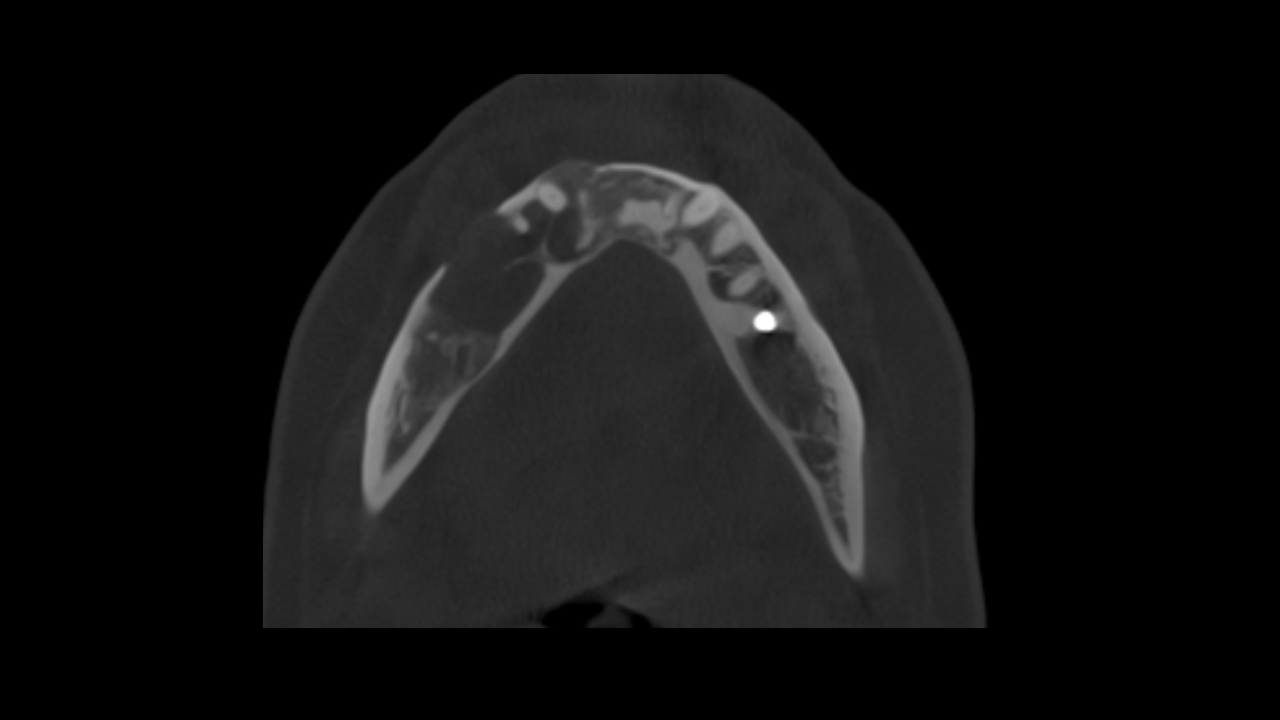

Study 3

Finding: There is an osteolytic lesion involving the right mandibular arch, characterized by effacement and expansion of the buccal and lingual cortices. Notably, there is destruction of the alveolar crest, and the cortical boundaries of the mandibular canal are eroded. These imaging findings are highly suggestive of a malignant lesion.